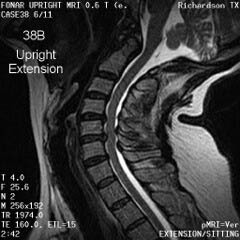

Cervical Spine |

|

Upright Neutral |

Upright Extension |

Unsuspected

Disc Herniation in Extension |